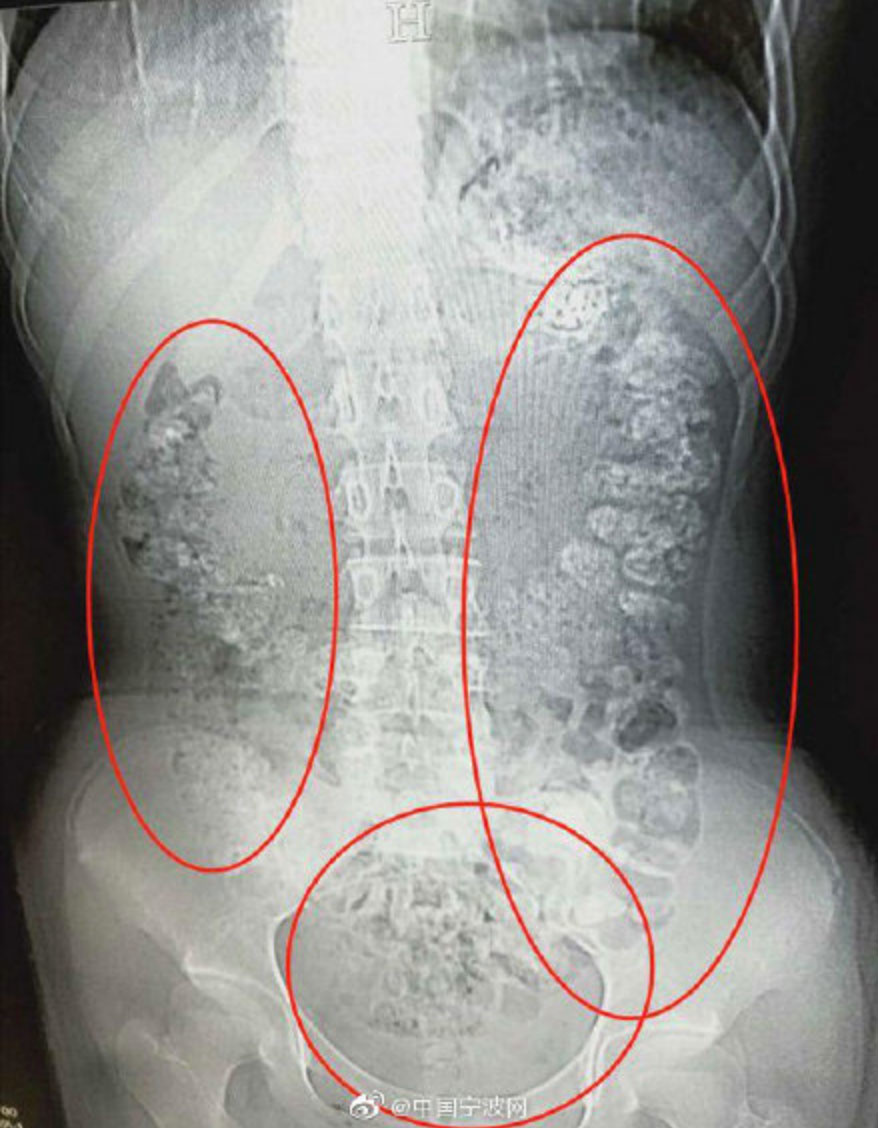

According to reports, the (unnamed) teen, who lives in the Zhejiang province of China, was taken to the hospital when she complained that she’d spent nearly a week in terrible stomach pain and unable to eat. When doctors couldn’t find anything wrong with a physical exam, they decided to do some imaging, which (allegedly) led to the following picture:

See those strange, scary-looking shadows? The ones that look like they came directly from PR for a horror movie? Doctors deduced that they were approximately 100 boba pearls that had not been digested. The teen admitted that she’d had one cup of boba in the past few days, but her medical team (and Dr. Gregory House) thought she just might be trying to hide the fact that she’d been scoffing down those pearls like it was her literal job. (Although I’ve never counted how many pearls you get in a cup of boba. Is it more or less than 100?) (Maybe she digested a whole lot more.)

Alexis Mascitti, a New York-based MD and consultant who I spoke with for this story, told me that while the x-ray above shows “fecal impaction,” it’s impossible to tell whether the teen’s severe constipation came from boba pearls just by looking at the image. Mascitti has, however, seen undigested boba pop up on abdominal x-rays before, so it’s not far-fetched that the pearls are the culprit here.